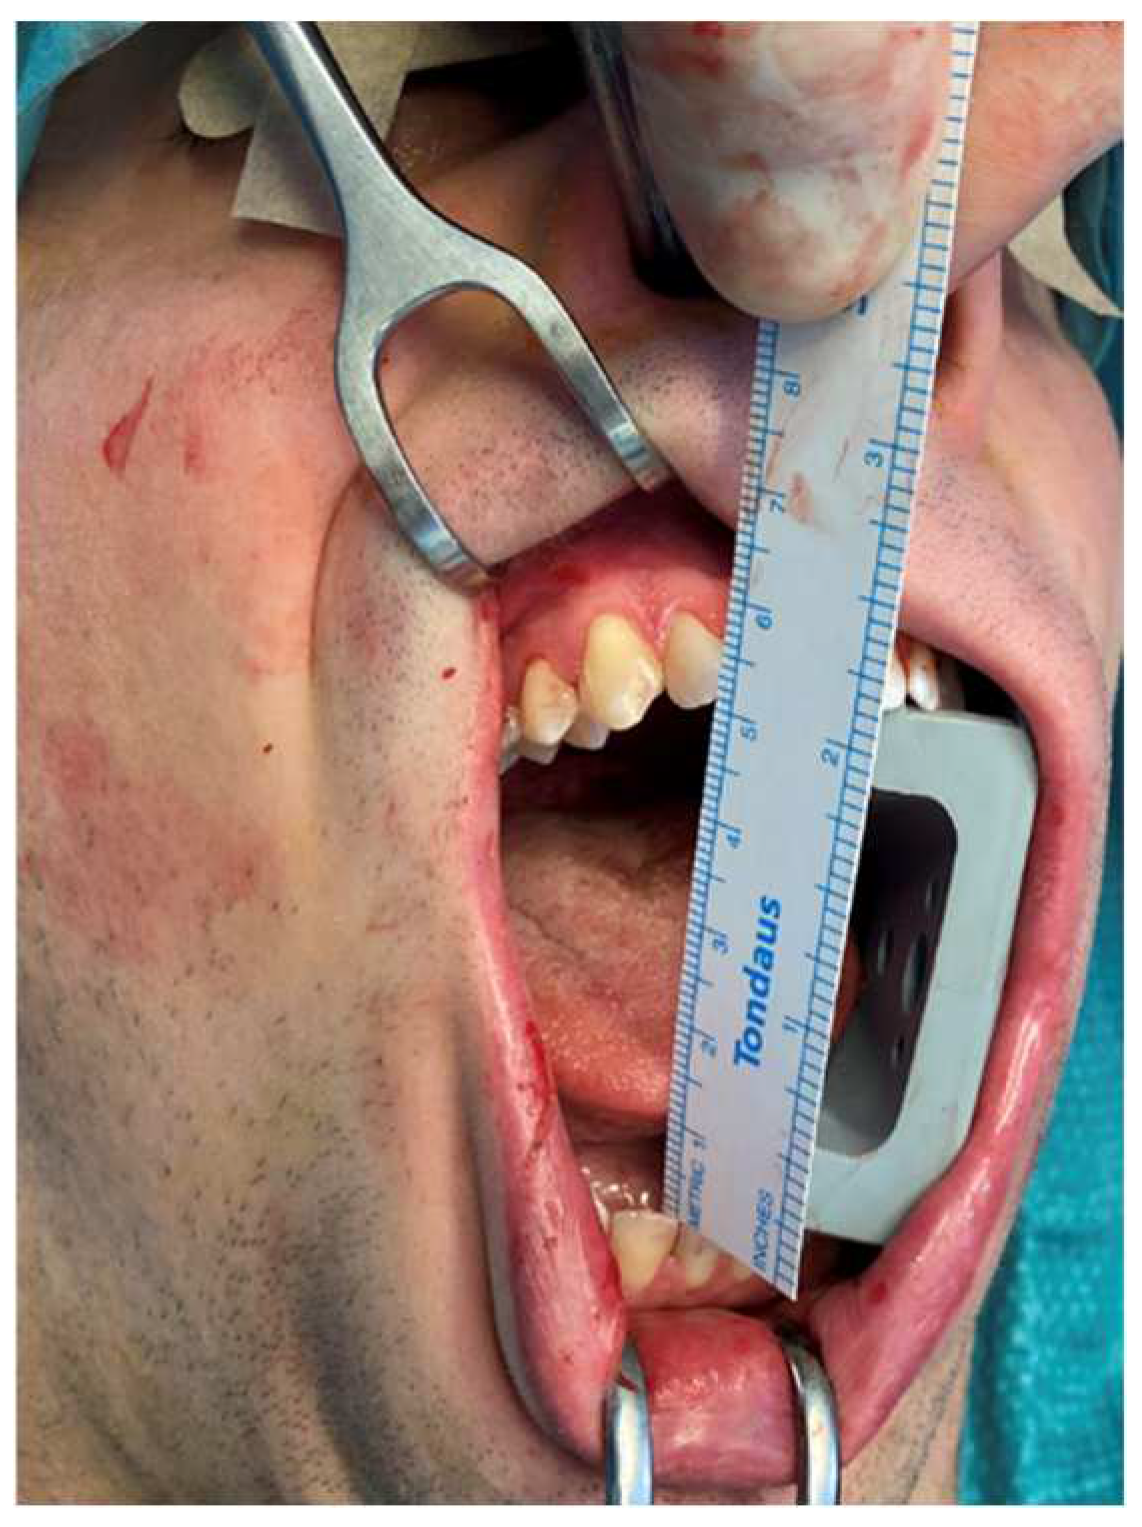

| 114 | Raccampo et al. | 2022 | 19 | F | R | CCE | 25 | 40 | Intraoral coronoidectomy | 12 | No |

| 115 | Raccampo et al. | 2022 | 18 | M | R | OC | 20 | 44 | Intraoral coronoidectomy | 12 | No |

| 116 | Raccampo et al. | 2022 | 23 | M | R/L | CH | 20 | 37 | Intraoral coronoidectomy | 14 | No |